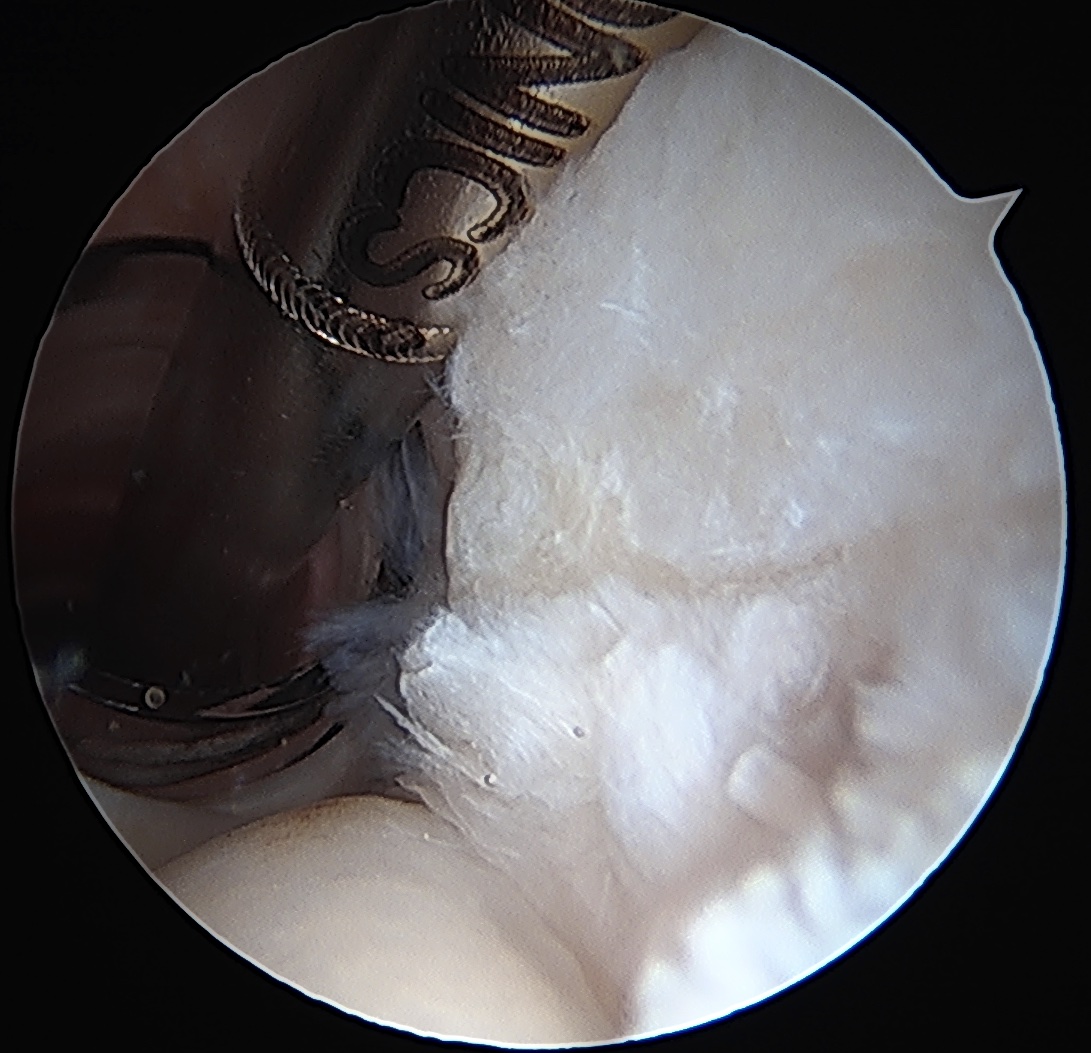

Arthroscopy

Articular side

Normal insertion of undersurface of the rotator cuff onto the footprint, with camera in glenohumeral joint

> 50% uncovering of footprint in glenohumeral joint